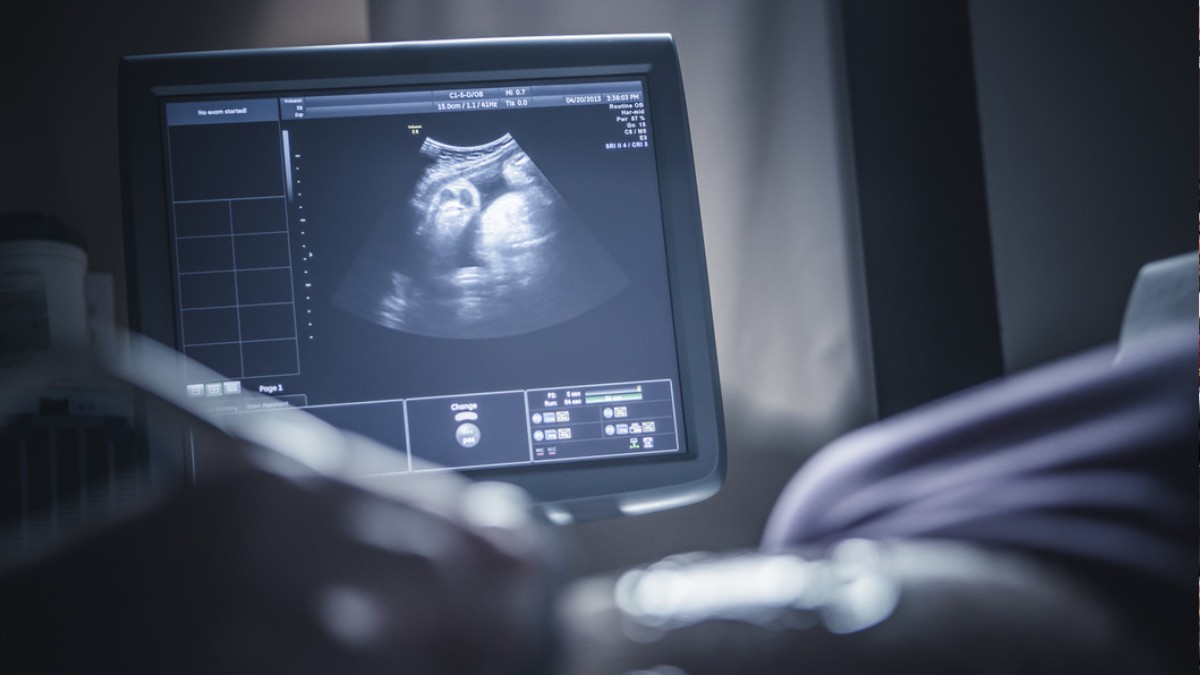

La información fue difundida por la cadena Al Arabiya tras un diagnóstico ecográfico que dejó asombrados incluso a los propios médicos.